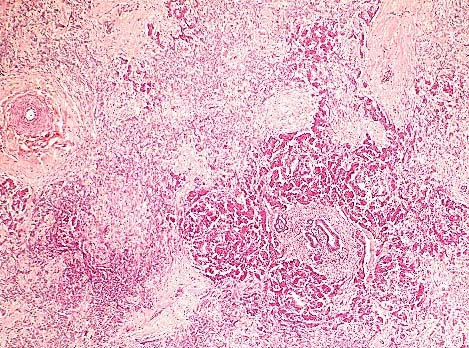

Diffuse mesenteric and pancreatic atrophy and fibosis due to zinc toxicosis resulting from ingestion of a penny. (HE, 40X, 59K)

AFIP Diagnosis: 1. Pancreas: Exocrine parenchymal loss, diffuse, moderate, with regeneration, fibrosis and ductular hyperplasia, American eider duck (Somateria mollissima dresseri), avian. 2. Serosa: Serositis, fibrinosuppurative, subacute, moderate to severe, with gram-negative bacilli. 3. Omental adipose tissue: Atrophy, multifocal, moderate.

Conference Note: Cases of zinc toxicosis in animals usually result from ingestion of galvanized fence clips or pennies. The histologic and ultrastructural lesions of experimental zinc toxicity in ducklings, chicks, and sheep have been described.

Several distinct syndromes have been reported following ingestion of zinc-containing objects. A zinc-induced hemolytic anemia has been described in a puppy following ingestion of pennies. An experimental study in sheep suggests that the primary lesion in zinc toxicosis is pancreatic ductular necrosis. The early lesions described in sheep include necrosis of the pancreatic ductular epithelium, periductular inflammation, and interlobular fat necrosis, followed by edema, lobular cystic change, atrophy, fibrosis, and ductular hyperplasia. Necrotizing enteritis and renal tubular necrosis have also been reported in birds.